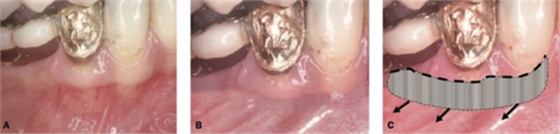

該方式齦瓣固定的效果差,術(shù)后血供差,為了改善血供,我們提倡下面的改良縫合方式,血供更好,成功率更高,如下圖:

通過用縫線壓迫的方式固定,術(shù)后愈合的過程齦瓣始終與受區(qū)骨膜貼合,而不會移動。

但是該方法對于縫合技術(shù)要求較高,因此本人嘗試了新的方法,膜釘固定:

該方法操作簡單,但是需要擇期局麻下拆除膜釘。

國外還有一種更加簡便的方法,使用生物膠粘接固定,如下圖: